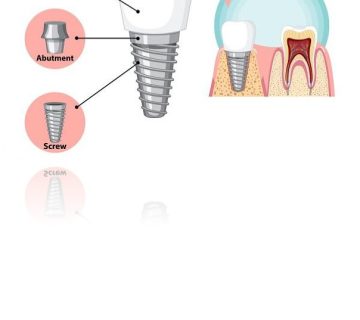

افراد در هنگام صحبت کردن و غذا خوردن کاملا احساس راحتی می کنند. ایمپلنت شامل 3 بخش اصلی فیکسچر، اباتمنت و تاج دندان است. فیکسچر یکی از اجزای ایمپلنت است که درون استخوان فک کاشته می شود و با استخوان اتصال محکمی برقرار می کند.